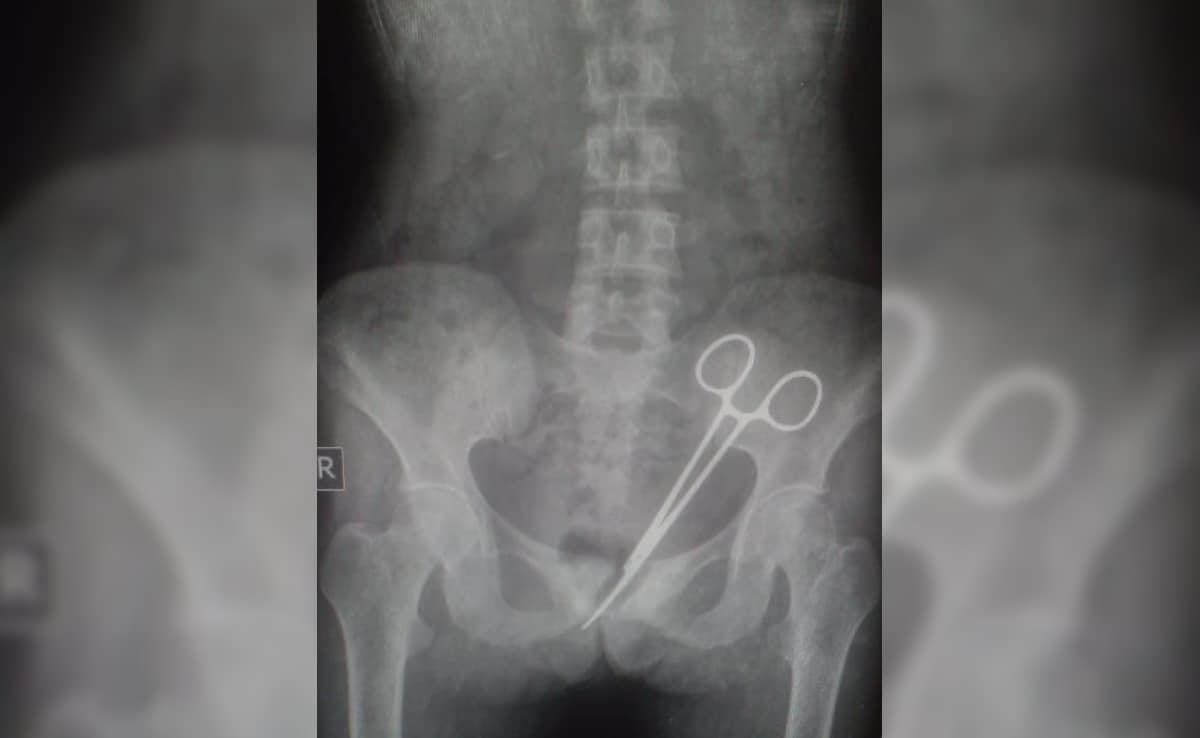

एक महिला के पेट में 12 साल तक कैंची (Surgical scissors) पड़ी रही और इस लंबे समय में डॉक्टर इसका पता नहीं लगा पाए, जबकि महिला इतने साल तक पीड़ा सहती रही. सिक्किम (Sikkim) में यह मामला सामने आया है. डॉक्टरों ने 12 साल पहले सर्जरी में लापरवाही बरती थी और कैंची पेट में छोड़ दी थी. अब 12 साल बाद जब पता चला तो डॉक्टरों ने पेट की सर्जरी करके कैंची निकाल दी है.

सिक्किम के एसटीएनएम अस्पताल में यह चौंकाने वाला मामला सामने आया. यहां एक महिला की 8 अक्टूबर को एक बड़ी सर्जरी की गई. सर्जरी के जरिए सन 2012 में अपेंडिक्स ऑपरेशन के बाद एक दशक से भी अधिक समय तक महिला के पेट में पड़ी सर्जिकल कैंची को निकाला गया.

महिला के पति ने बताया कि उसकी पत्नी ने 2012 में पुराने एसटीएनएम अस्पताल में अपेंडिक्स की सर्जरी कराई थी. सर्जरी के बाद उसे लगातार गंभीर पेट दर्द होने लगा. आश्चर्य की बात है कि इसके बाद वर्षों तक महिला के पेट में पड़ी सर्जिकल कैंची का पता नहीं चला. जब 8 अक्टूबर को डॉक्टरों ने उसके परीक्षणों में उसके पेट में सर्जिकल कैंची देखी तो तुरंत उसकी सर्जरी की गई.

अस्पताल में चिकित्सा विशेषज्ञों की एक टीम ने 8 अक्टूबर को कैंची को निकालने के लिए महिला की सर्जरी की. महिला की हालत स्थिर है और वह स्वस्थ हो रही है. मरीज के पेट में सर्जिकल कैंची होने का एक दशक से अधिक समय तक पता नहीं चला. इससे चिकित्सा में लापरवाही, रोगी की सुरक्षा और अस्पताल के प्रोटोकॉल को लेकर गंभीर सवाल उठ रहे हैं.